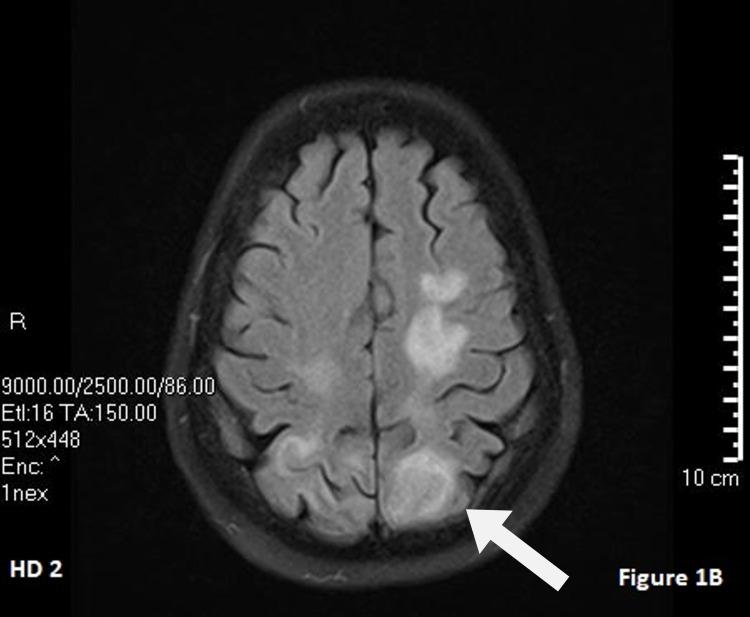

Posterior reversible encephalopathy syndrome (PRES) is a complex process that has been implicated in the setting of many chronic diseases (i.e., hypertension, chronic kidney disease, autoimmune diseases, infections, transplant treatments, etc.). The exact pathogenesis of PRES is still unclear; however, it has been suggested to involve endothelial injury leading to immune system activation and cytokine release. This case report examines an atypical presentation of PRES caused by serotonin-norepinephrine reuptake inhibitors (SNRIs).